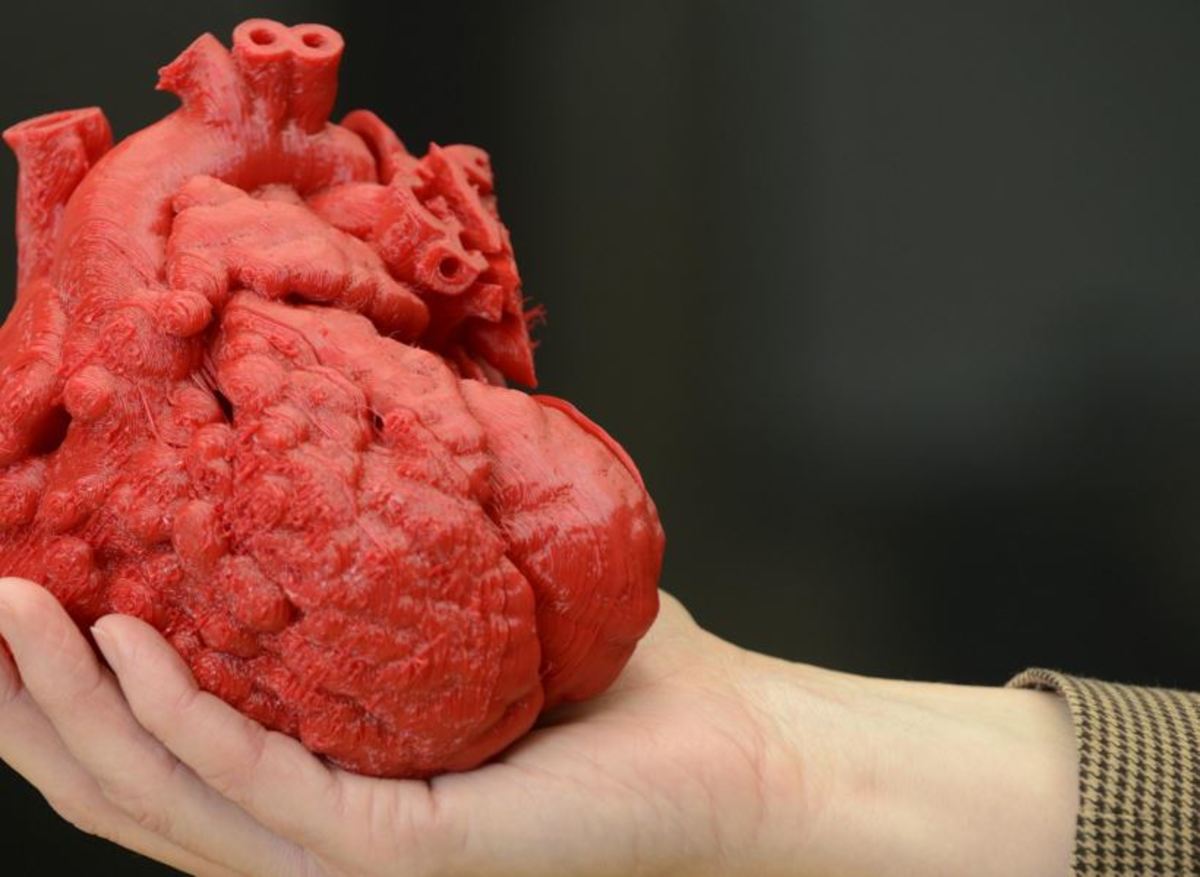

Τρισδιάστατη εκτύπωση καρδιάς. Η τεχνολογία της τρισδιάστατης απεικόνισης, σάρωσης και εκτύπωσης ανθρωπίνων οργάνων αποτέλεσε τον τομέα με την ταχύτερη εξάπλωση στον χώρο της ιατρικής.